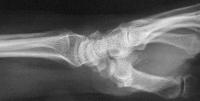

Palmar flexion of the scaphoid, lunate dorsiflexion.

Click for larger image

Scapholunate diastasis.